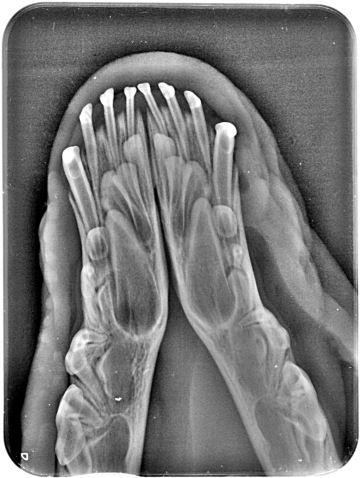

Diagnostics - intraoral X-ray

The x-ray of your pet's teeth is similar to that of humans. An x-ray machine using a small amount of radiation is used to view the inside of your dog's teeth and those areas below the gum line that are hidden. Unlike humans, animals must be under general anesthesia for a dental X-ray, as it is practically impossible to get them to hold the plate in their mouth and not bite into it. You can read more about the anesthesia itself and what it all entails here.

Animals just can't tell us when their teeth are sick and some never show that they are in pain. In many cases, an intraoral x-ray is the only way we can tell that your pet has a serious dental problem that can be treated and the discomfort alleviated.

It should be noted that quality dental treatment requires x-rays of the teeth. Without an x-ray of the teeth, it is practically impossible to assess the condition of the periodontium, and diseases that occur below the level of the gums are invisible to the human eye.

An X-ray should be taken every time a tooth is missing, discolored or broken. Furthermore, in cases of swollen and inflamed gums, growths in the mouth or even bad breath. Even without these symptoms, it is recommended to take pictures of at least strategic teeth - the teeth of the blockbuster complex and canines - always when removing tartar. Remember that one human year is equal to 5-7 dog years, and humans routinely get dental x-rays at least once every 2 years for a preventative checkup.